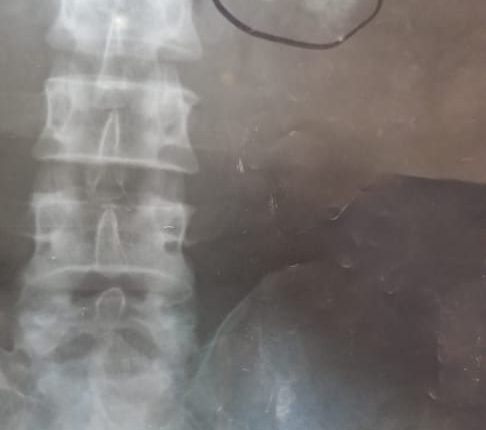

أجريت بهيئة المستشفى الجمهوري محافظة حجة عملية جراحية لإزالة أكثر من 30 حصوة من كلية مواطن يبلغ من العمر 45 عاما.

وأوضح أخصائي جراحة الكلى والمسالك البولية بالهيئة الدكتور مرتضي الشرعبي أن العملية تعد من العمليات النادرة نظرا لعدد الحصوات التي تم إزالتها من كلية المريض اليسرى.